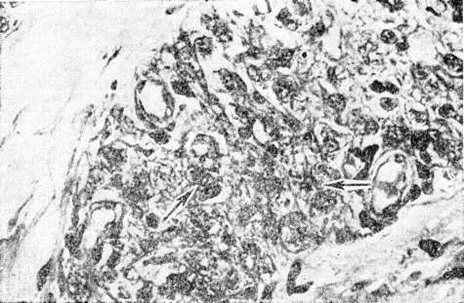

Электронно-микроскопическими исследованиями установлено, что ультраструктура возбудителя Лепра принципиально не отличается от строения других видов грамположительных бактерий. На поверхности микобактерий Лепра выявляется равномерный электроннопроницаемый (осмиофобный) слой толщиной 5—10 нанометров (наружный диффузный слой клеточной стенки). За ним следует осмиофильный слой клеточной стенки толщиной от 3 до 10 нанометров, состоящий из двух очень тонких некоторое, плотно прилегающих друг к другу. Непосредственно к внутренней поверхности клеточной стенки примыкает наружный слой цитоплазматической мембраны (рисунок 1), представляющей собой, как и у других бактерий, трёхслойную мембрану толщиной 7,5—9 нанометров. В бактериальной клетке встречаются 1—2 мезосомы с выраженным полиморфизмом (петлеобразные, везикулярные, трубчатые, пластинчатые, гроздевидные). В цитоплазме выявляется сравнительно небольшое количество рибосом, сферические электронно-плотные включения волютина диаметром 20—50 нанометров, включения, имеющие вид ограниченных мембраной вакуолей (предположительно липоиды), и гомогенные тельца, природа которых остаётся неизвестной. Ядро не имеет определённой формы, расположено в центре клетки вдоль её длинной оси, не ограничено мембраной. Иногда в лизирующихся под воздействием химиотерапии клетках микобактерий Лепра выявляются спороподобные образования (рисунок 2 и 3).

Основным способом размножения микобактерий Лепра является деление материнской клетки и врастания поперечной перегородки. Микобактерия Лепра является облигатным внутриклеточным паразитом тканевых макрофагов или клеток ретикулоэндотелиальной системы, проявляет выраженный тропизм к коже и периферическим нервам, но на поздних стадиях развития процесса встречается также во многих других клетках и тканях организма. В тканевой клетке микобактерии Лепра размножаются только в цитоплазме (рисунок 4); внутриядерный паразитизм для них нехарактерен. Микобактерии в лепрозных клетках иногда отграничены от цитоплазмы клетки-хозяина фагосомной мембраной. На поздних стадиях инфекции паразитирование возбудителей Лепра человека сопровождается нарушением строения эндоплазматического ретикулума и митохондрий клетки-хозяина.